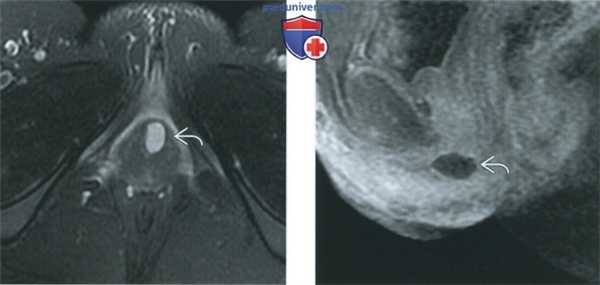

(Слева) При МРТ на Т2-ВИ FS в аксиальной плоскости визуализируется простая киста железы Скина, расположенная в передней части входа во влагалище.

(Справа) При МРТ на Т1-ВИ FS в сагиттальной плоскости с контрастированием у той же пациентки киста железы Скина имеет однородную структуру, дает гипоинтенсивный сигнал, не усиливающийся после введения контрастного вещества. Выявление в кисте солидного компонента или солидного объемного образования у наружного отверстия уретры, демонстрирующих усиление сигнала при введении контрастного вещества, должно вызвать подозрение на злокачественную трансформацию кисты.